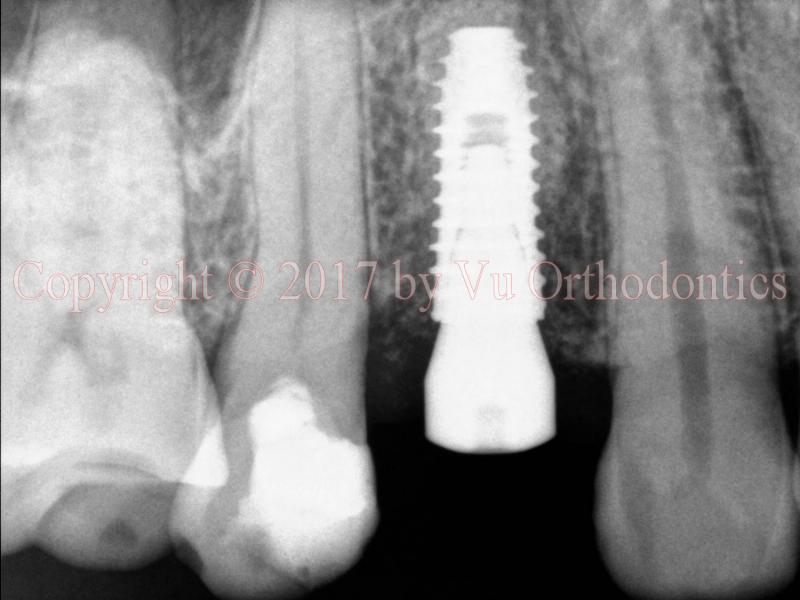

In this case of a single implant, a fully-guided system is used. The implant is perfectly placed center, between the roots of the two natural teeth (Fig. 5). PA means periapival; BW means bitewing. The implant is placed such that its platform is about 0.5-1 mm apical from the alveolar crest.

Fig. 5. A good implant placement: (a) implant and healing abutment (PA view), (b) implant and healing abutment (BW view), and (c) implant, implant abutment, and implant crown (PA view, a month later)